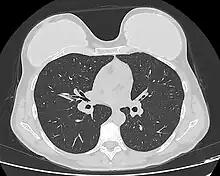

Silicone implant rupture can be evaluated using magnetic resonance imaging; from the long-term MRI data for single-lumen breast implants, the European literature about second generation silicone-gel breast implants (1970s design), reported silent device-rupture rates of 8–15 per cent at 10-years post-implantation (15–30% of the patients).[51][52][53][54]

The study Safety and Effectiveness of Mentor's MemoryGel Implants at 6 Years (2009), which was a branch study of the U.S. FDA's core clinical trials for primary breast augmentation surgery patients, reported low device-rupture rates of 1.1 per cent at 6-years post-implantation.[55] The first series of MRI evaluations of the silicone breast implants with thick filler-gel reported a device-rupture rate of 1 percent, or less, at the median 6-year device-age.[56] Statistically, the manual examination (palpation) of the woman is inadequate for accurately evaluating if a breast implant has ruptured. The study, The Diagnosis of Silicone Breast implant Rupture: Clinical Findings Compared with Findings at Magnetic Resonance Imaging (2005), reported that, in asymptomatic patients, only 30 per cent of the ruptured breast implants are accurately palpated and detected by an experienced plastic surgeon, whereas MRI examinations accurately detected 86 per cent of breast implant ruptures.[57] Therefore, the U.S. FDA recommended scheduled MRI examinations, as silent-rupture screenings, beginning at the 3-year-mark post-implantation, and then every two years, thereafter.[24] Nonetheless, beyond the U.S., the medical establishments of other nations have not endorsed routine MRI screening, and, in its stead, proposed that such a radiologic examination be reserved for two purposes: (i) for the woman with a suspected breast implant rupture; and (ii) for the confirmation of mammographic and ultrasonic studies that indicate the presence of a ruptured breast implant.[58]

Furthermore, The Effect of Study design Biases on the Diagnostic Accuracy of Magnetic Resonance Imaging for Detecting Silicone Breast Implant Ruptures: a Meta-analysis (2011) reported that the breast-screening MRIs of asymptomatic women might overestimate the incidence of breast implant rupture.[59] In the event, the U.S. Food and Drug Administration emphasised that "breast implants are not lifetime devices. The longer a woman has silicone gel-filled breast implants, the more likely she is to experience complications."[60]